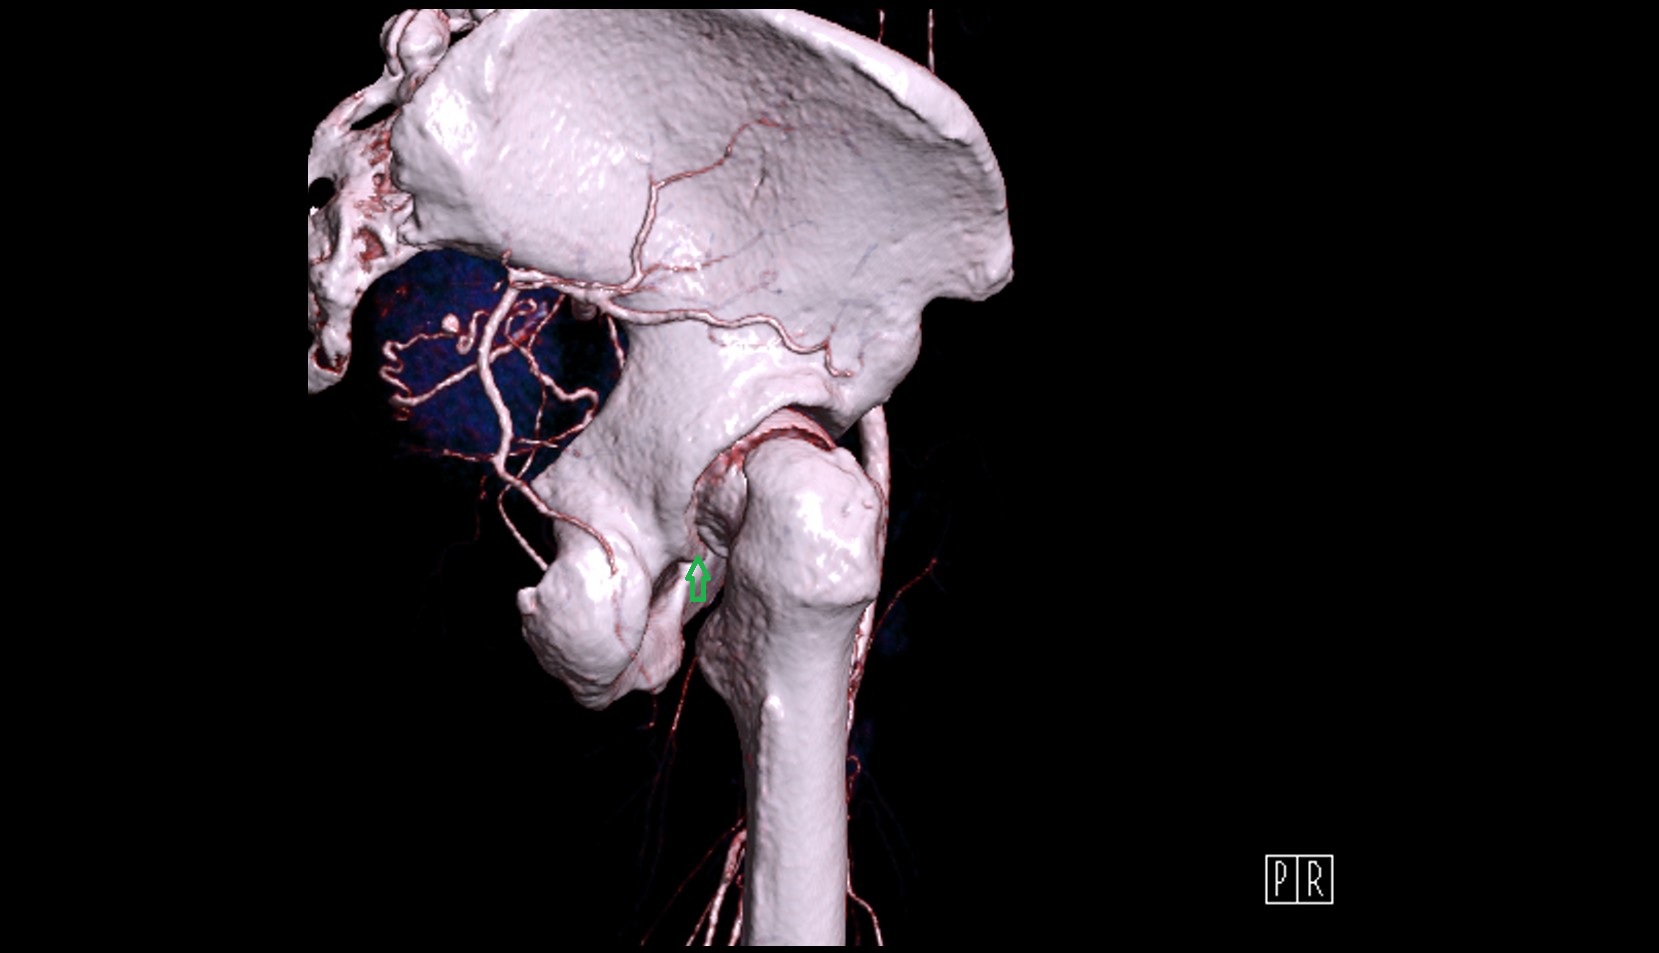

- Internal carotid artery

- Brachiocephalic trunk

- Carotid bifurcation

- Common carotid artery

- External carotid artery

- Internal carotid artery (cervical part)